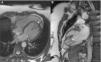

A 36-year-old woman was referred for medical evaluation prior to non-cardiac surgery. She was healthy and only complained of sporadic palpitations. The 12-lead electrocardiogram showed sinus rhythm and left bundle branch block. Transthoracic echocardiography revealed a normally functioning, slightly dilated left ventricle (LV), with the interventricular septum bulging toward the right ventricle (RV), which was elongated and wrapped around the LV (Figure 1; Supplementary material Videos S1 and S2). The papillary muscles were structurally abnormal and presented an apical origin, findings better visualized in contrast images (Figure 2; Videos S3–S5). Cardiac magnetic resonance confirmed the presence of a truncated LV, a complex network of papillary muscles of apical origin, and a banana-shaped, normally functioning RV (Figures 3 and 4; Videos S6–S8). There was no evidence of fatty infiltration or late enhancement with gadolinium.